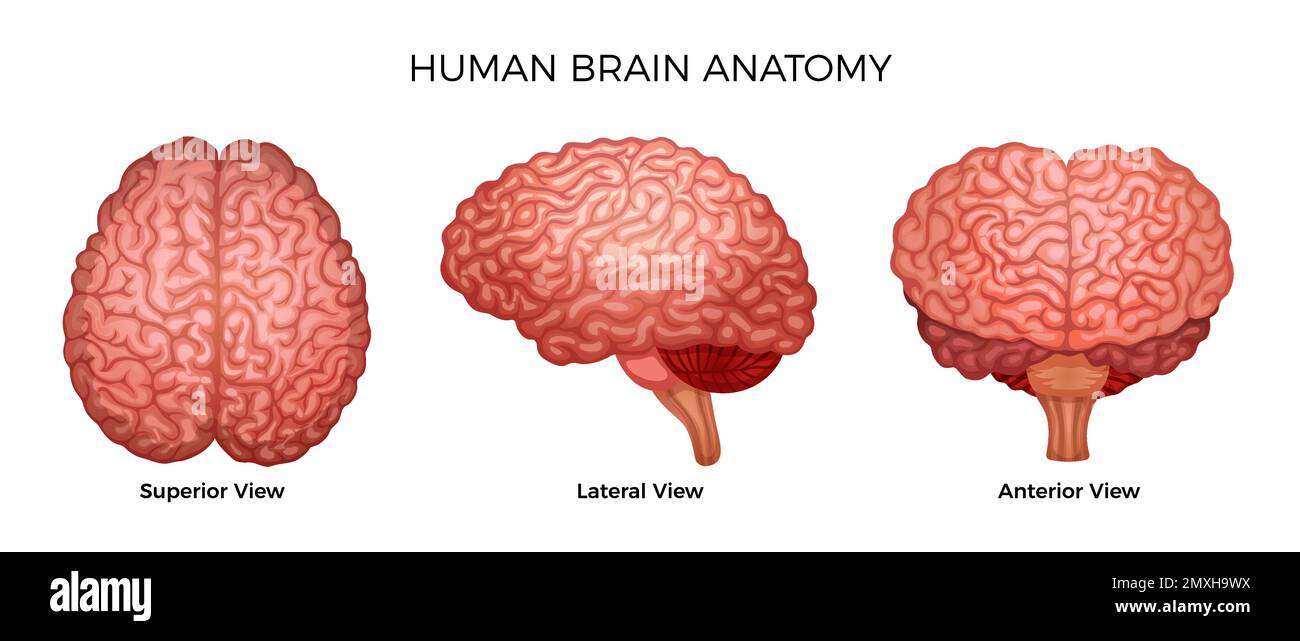

RF2MXH9WX–Anatomia cerebrale umana Set di colori di viste laterali e anteriori superiori della corteccia cerebrale con giro cerebrale isolato su fondo bianco illust vettoriale

RF2Y8XEWG–Anatomia del cervello umano. Emisferi cerebrali, corteccia cerebrale, frontale, parietale, temporale, lobi occipitali, cervelletto e tronco cerebrale, fessura cerebrale.